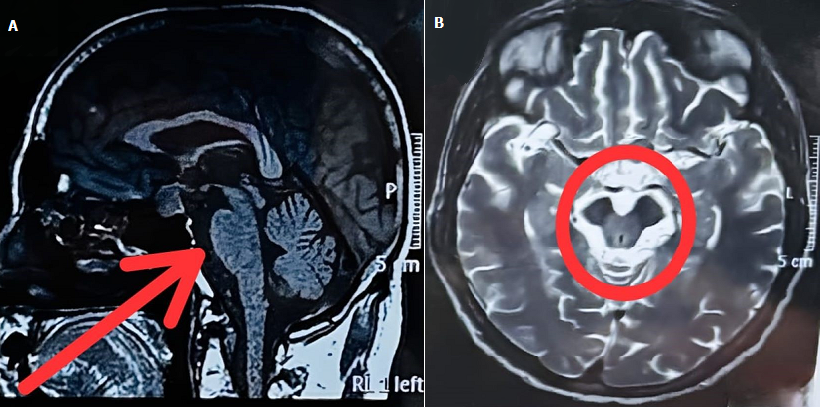

Distinctive magnetic resonance imaging features of progressive supranuclear palsy with cerebellar phenotype: hummingbird and Mickey Mouse signs

A patient in their 60s presented with a progressive history over two years of unsteadiness of gait, frequent falls, impaired coordination, and slurred speech. Neurological examination revealed axial rigidity, bradykinesia, intentional tremors of the upper limbs, wide-based ataxic gait, limb dysmetria, impaired rapid alternating movements, and increased tone with cogwheel rigidity. Vertical gaze palsy consistent with supranuclear ophthalmoplegia was noted. These clinical features are indicative of progressive supranuclear palsy (PSP) with cerebellar involvement. The magnetic resonance imaging findings revealed, in the sagittal T1-weighted sequence (A: red arrow), marked atrophy of the midbrain tegmentum with relative preservation of the pons, producing the classical "hummingbird sign" (also known as the "penguin sign"), an established neuro-imaging hallmark supportive of PSP diagnosis. Significant atrophy of the cerebellum, particularly affecting the vermis and hemispheres, contributes to the enlargement of the fourth ventricle. The axial T2-weighted sequence (B: red circle) at the midbrain level shows characteristic atrophy with reduction in the anteroposterior diameter of the midbrain tegmentum, consistent with the "Mickey Mouse sign", another well-recognised radiologic marker supportive of PSP. Cerebellar atrophy is evident as volume loss in the cerebellar hemispheres, visible on these axial slices. Together, these clinical and imaging findings confirm the diagnosis of the cerebellar phenotype of PSP (PSP-C). Recognition of this variant is essential for guiding management, which primarily involves supportive care through physiotherapy and occupational therapy, as pharmacological treatment responses are typically limited. Early diagnosis facilitates fall prevention strategies, tailored rehabilitation, and patient and caregiver counselling regarding disease progression.